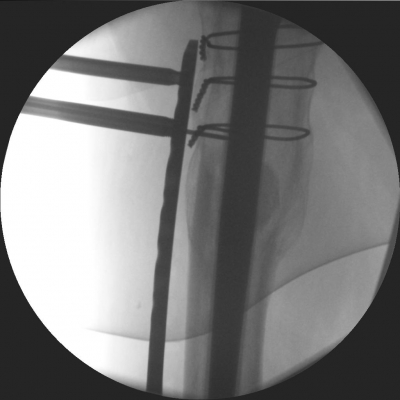

Proximal temporary fixation with K-wires. Proximal temporary fixation with K-wires. View the embedded image gallery online at: https://www.zbinetworkemea.com/fracture/index.php/treatment-example/vancouver-c-simple/item/131-preliminary-fixation#sigProId934bbf1227 Preliminary Fixation After the plate is inserted it is fixed temporarily with K-wires proximally and distally. Avoid hitting the prosthesis with the K-wire.